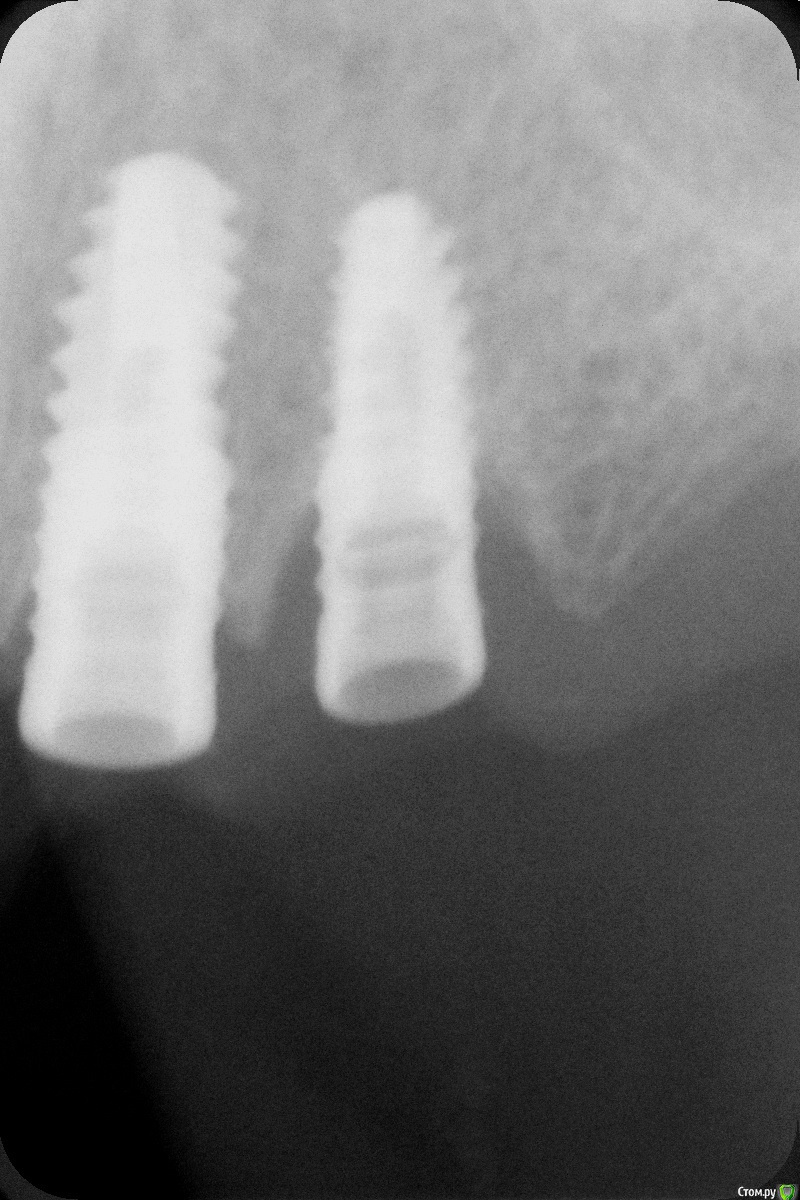

johniola Опубликовано 16 января, 2015 Поделиться Опубликовано 16 января, 2015 Мужики,что за импланты?от израиля ключи не подходят. Ссылка на комментарий

Alejandro Опубликовано 17 января, 2015 Поделиться Опубликовано 17 января, 2015 Хотя на mis seven сильно похожи Ссылка на комментарий

johniola Опубликовано 19 января, 2015 Автор Поделиться Опубликовано 19 января, 2015 узнал,это 3i , уже всё достал 2 Ссылка на комментарий

gum Опубликовано 21 января, 2015 Поделиться Опубликовано 21 января, 2015 Да на 3 Ай похоже но у них еще лепестки есть а здесь что то не видно Ссылка на комментарий

Kurz1981 Опубликовано 28 января, 2015 Поделиться Опубликовано 28 января, 2015 Похоже действительно Biomet3i http://whatimplantisthat.com/wp-content/uploads/2012/03/OSSEOTITE-Tapered-Certain-4.jpg Ссылка на комментарий